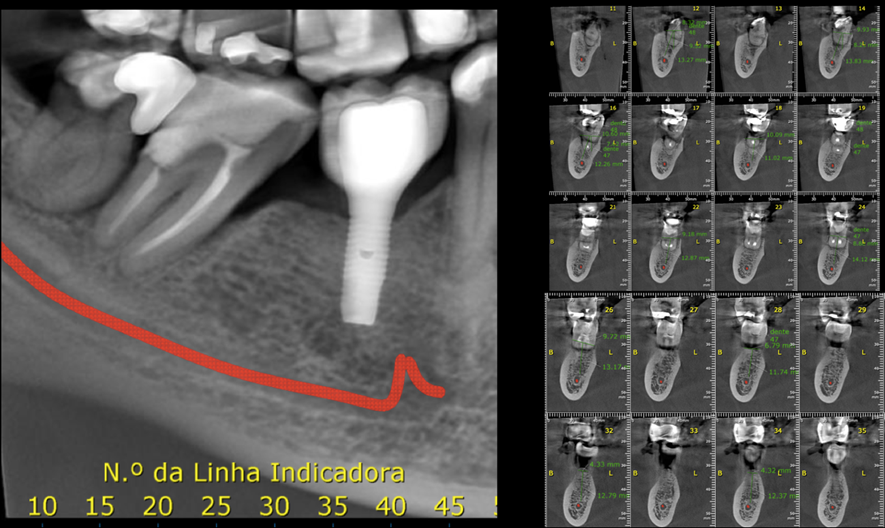

Figura 1 – Cortes tomográficos da região de molares inferiores direito. Observar a presença já de um implante na região equivalente aos elementos 45/46. Observar também a boa disponibilidade óssea na região.